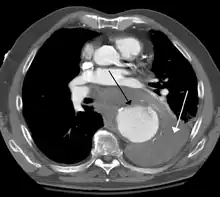

A thoracic aortic aneurysm is an aortic aneurysm that presents primarily in the thorax.

A thoracic aortic aneurysm is the "ballooning" of the upper aspect of the aorta, above the diaphragm. Untreated or unrecognized they can be fatal due to dissection or "popping" of the aneurysm leading to nearly instant death. Thoracic aneurysms are less common than an abdominal aortic aneurysm.[2] However, a syphilitic aneurysm is more likely to be a thoracic aortic aneurysm than an abdominal aortic aneurysm. This condition is commonly treated via a specialized multidisciplinary approach with both vascular surgeons and cardiac surgeons.